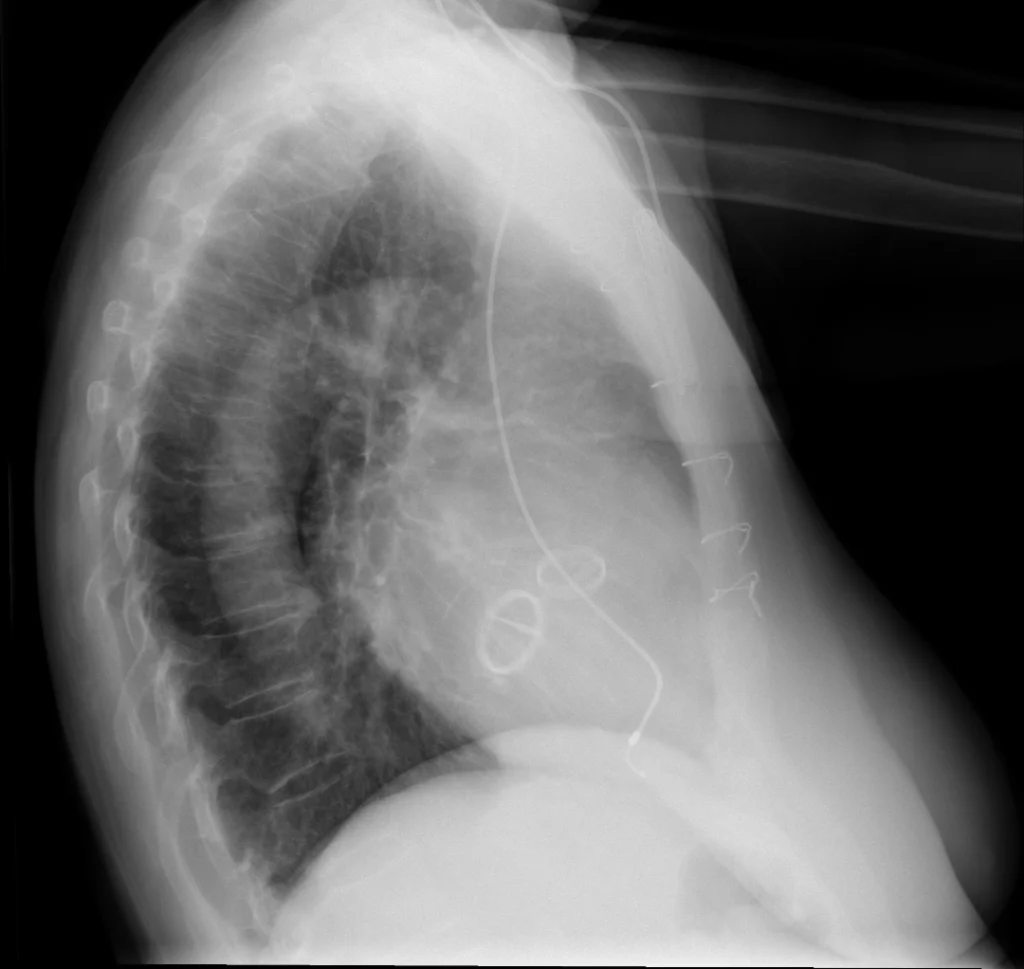

Rx de tórax lateral. Sutura esternal, válvulas mecánicas aórtica y mitral y marcapasos cardiaco unicameral con densidad metálica. Signos de espondilosis dorsal.